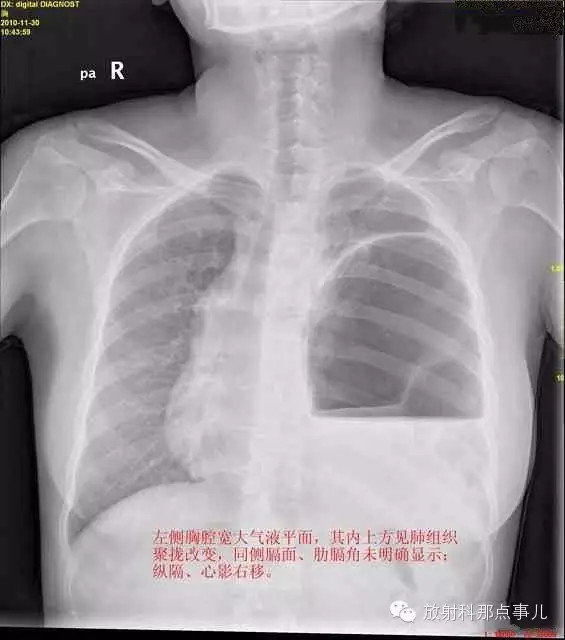

• 【病例学习】膈疝一例X线诊断

【病例学习】膈疝一例X线诊断